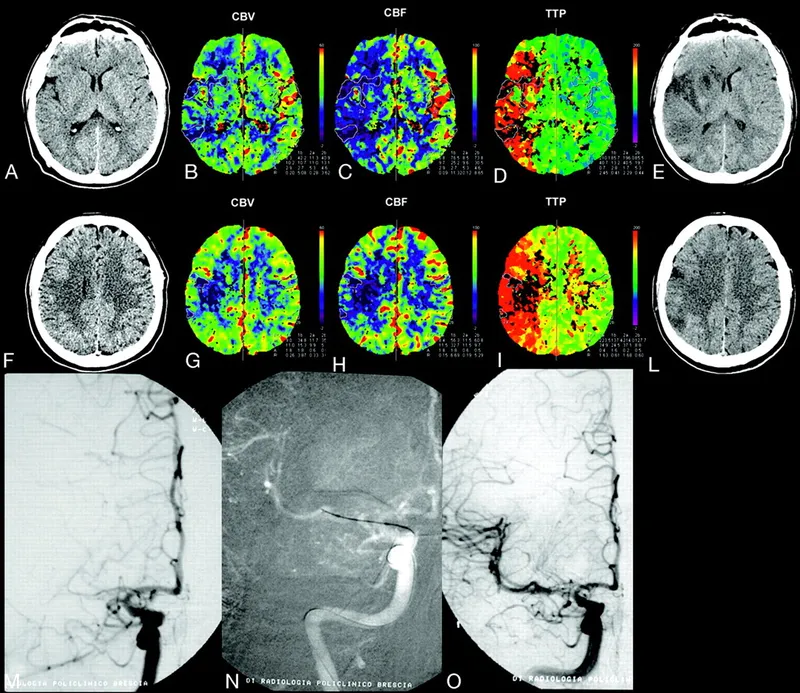

⭐ The DAWN and DEFUSE 3 trials radically extended the window to 24 hours for select patients demonstrating a "clinical-core mismatch" on advanced imaging (e.g., CT perfusion), where a small infarct core contrasts with a severe clinical deficit.

- Requires advanced imaging (CT Perfusion or DWI-MRI) to assess for mismatch.

- Mismatch: Small infarct core, large clinical deficit/penumbra.

⭐ High-Yield: The DAWN trial selected patients with a severe clinical deficit (NIHSS ≥ 10) but a small infarct core on imaging, demonstrating the principle of "tissue window" over "time window."

Expanded the mechanical thrombectomy (MT) window beyond 6 hours by prioritizing brain tissue status over strict time cutoffs. Patient selection relies on identifying a mismatch between the clinical deficit or salvageable tissue and the actual infarct size using advanced imaging.

- Criteria: High NIHSS score (≥10) despite a small infarct core on imaging. This mismatch implies a large salvageable penumbra.

- Criteria: Favorable perfusion imaging profile: small infarct core (<70 mL) and a penumbra-to-core volume ratio ≥1.8.

⭐ These trials proved that selecting patients based on salvageable brain tissue ("tissue is brain") is superior to rigid time windows ("time is brain") for late-presenting large vessel occlusion strokes.